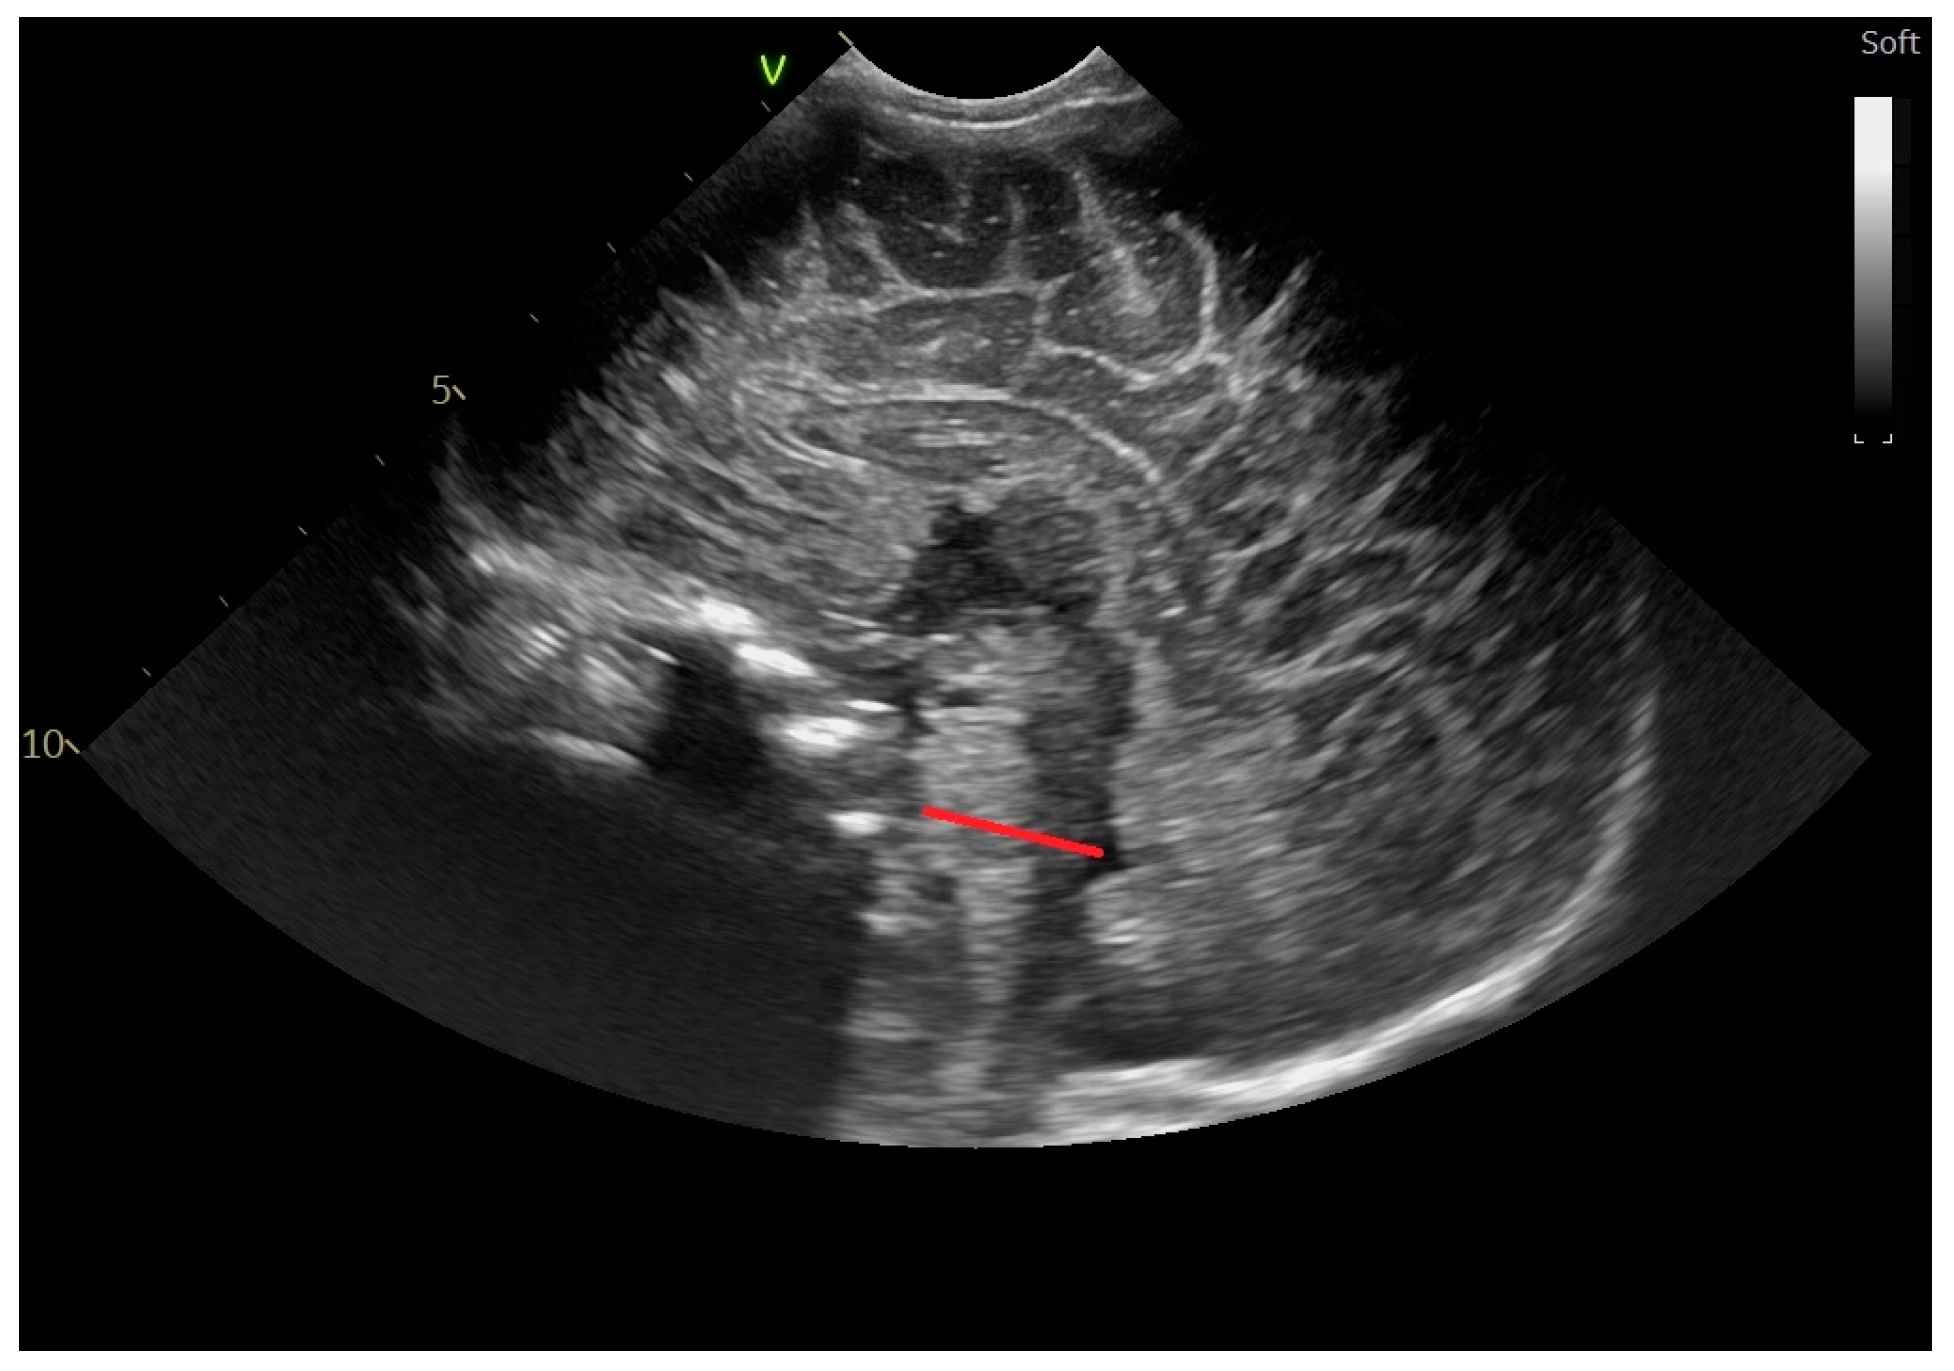

2.2. Head Ultrasound Measurements at TEA